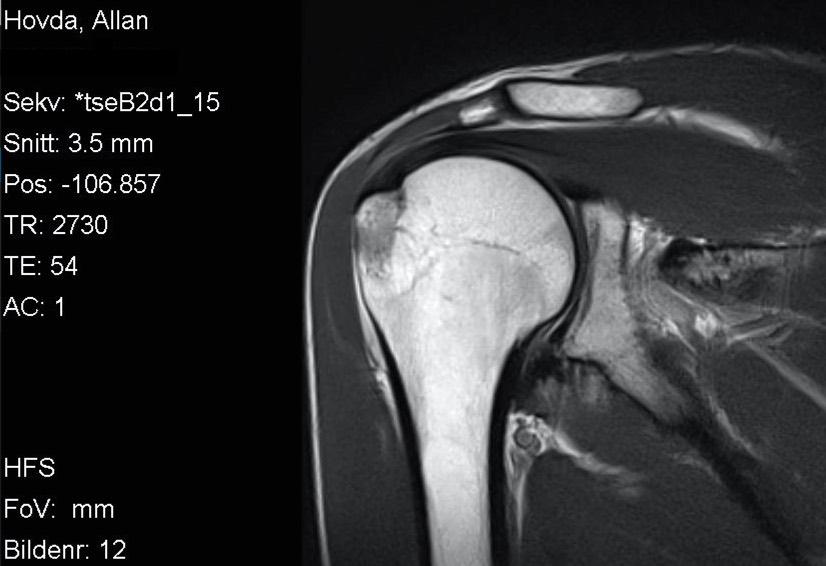

I forrige uke kom uansett svaret og resultatet var ikke akkurat helt som forventet. Nå var det riktig nok noe betennelse (aka bursitt) i skuldra som forventet men det var også et brudd i kanten på skuldra, såkalt tuberculum majos fracture på 2 x 2 cm. Så Kristian og Jørn Erik var rimelig overrasket over at jeg meldt tilbake at svømmingen gikk så bra.

Nå er det bare 6 dager til Ironman 70.3 Mallorca, og som alltid så ønsker jeg selvsagt å delta, men forstår at det kanskje ikke er det mest fornuftige. Om noen av dere har erfaringer eller gode råd/tips så tas de i mot med stor takk! Nå forstår jeg at radiolog er et eget yrke og tolking av MR-bilder krever mye erfaring og kunnskap, men jeg syntes ikke det ser såååå ille ut egentlig.

Skulderbilde